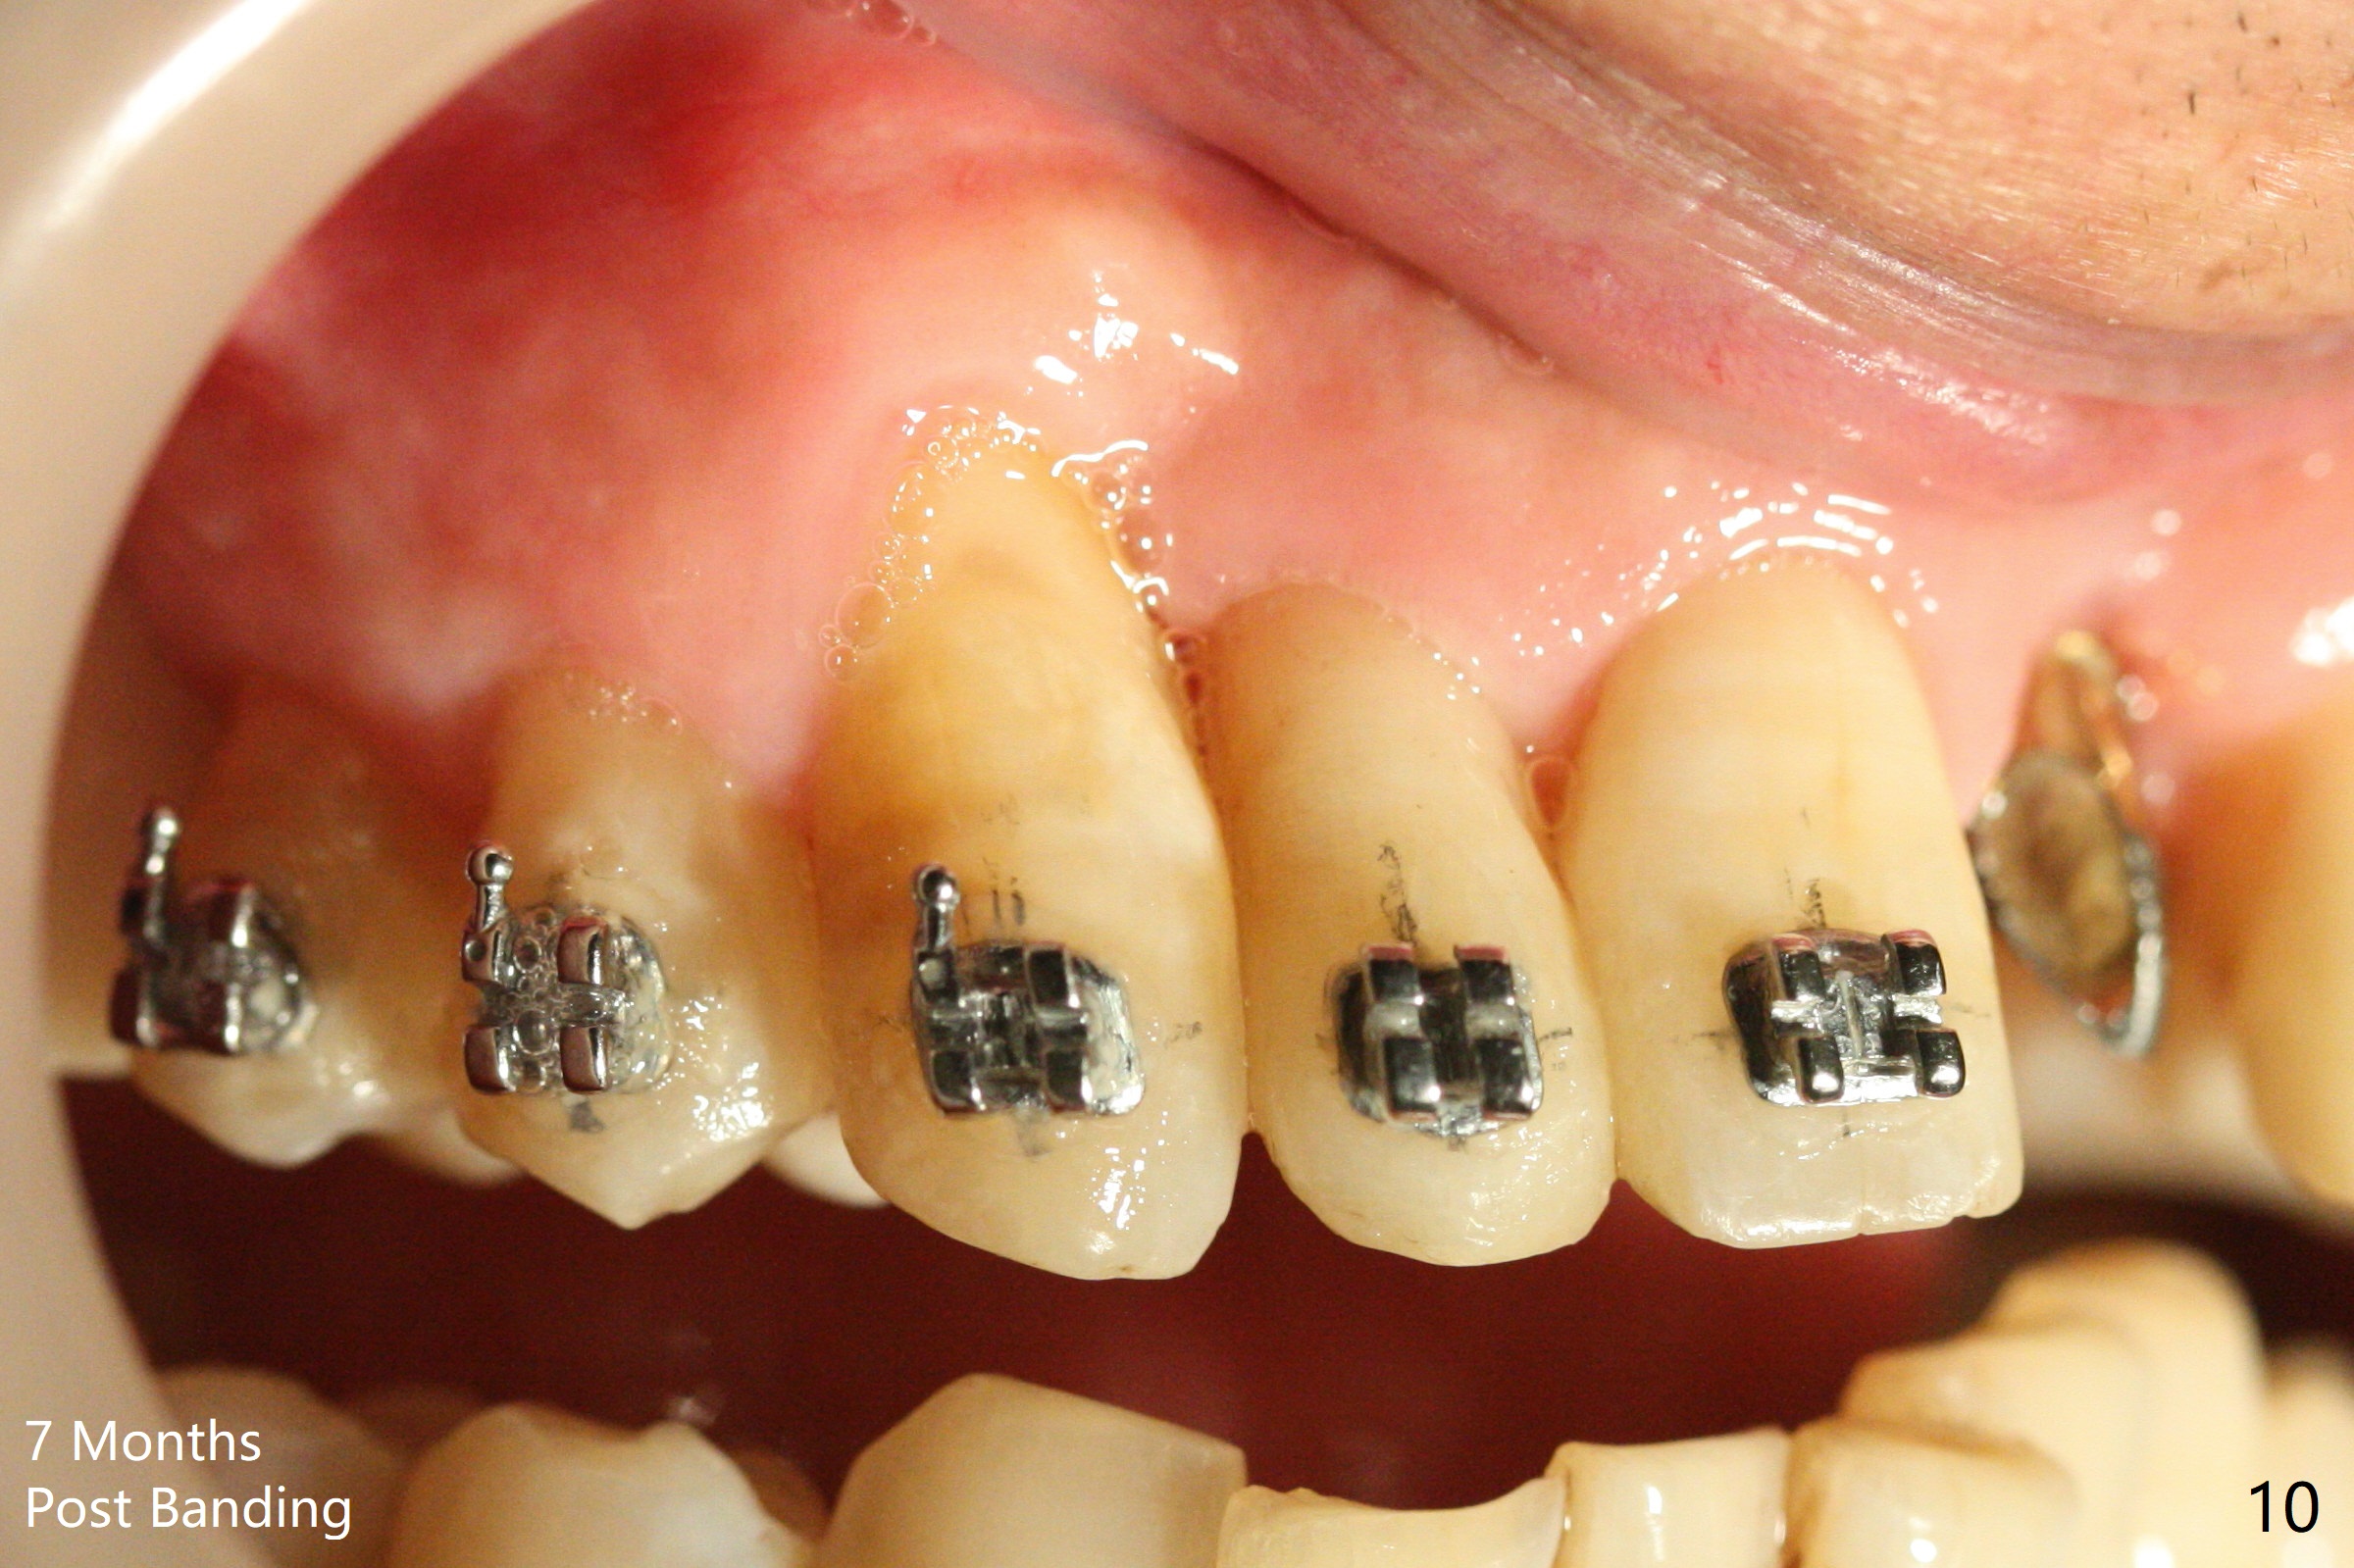

Nearly 7 months postop, the immediate provisional at UL1 is removed; with the mesial reduction of UL2 from 7 to 6 mm (Fig.1), an angled abutment is to be changed (4.5x15 degree, 2 mm cuff). A new provisional (Fig.2,3) co-incides with the facial midline. Brackets will be placed between UR4 to UL3 except UL2 (symptomatic once with chronic periodontitis) with initial proximal reduction between UR1-4 in preparation to correct cross bite of UR2. Twelve days later, the patient returns for UR5-UL3 bracketing after UR1-4 initial proximal reduction with 14 niti wire (Fig.4-6). UR1 moves mesial 20 days post open coil spring (Fig.7 arrow), while UL1 debracketes after permanent re-cementation of the temporary crown last visit (*, no re-bracketing, since it appears not essential). Before placement of 20 ss wire, diastemata are created by proximal reduction (Fig.8 *). In fact UR1 moves mesial, while UR3 does not move distal with the open coil. With placement of UR6 (implant) molar band, UR3 is distalized effectively. With sling shot, UR2 is almost labialized in one appointment (Fig.9). After consolidation of the diastemata between UR1-6 with power chains following UR2 cross bite correction (Fig.10), the restoration space for UL1 seems to be too large (Fig.11). Next visit, check the midlines, take 1-2 PAs for #7-9 and determine whether a straight abutment should be changed back and whether composite should be placed UR1 mesial to reduce the space. One week later, composite is added to the mesial surface of the tooth #8 to increase its width, while the provisional at #9 is relined to improve the interdental papilla (Fig.12). Minimal bone loss at UR2 is observed 8 months post banding (Fig.13), while the socket at UL1 seems to have healed except the most coronal 1 year 3 months postop (Fig.14 *). The margin of the abutment should be uneven, more coronal proximal than buccopalatal (Fig.15). The final crown has an open margin, partially due to less ideal trajectory (Fig.16 (black line: ideal trajectory, nearly 1 year 4 months postop)). Guided surgery could solve the problem. Sticky bone may restore the buccal plate defect. Die shows that the implant is palatally placed (Fig.17). CT will be taken to determine whether the implant perforates the palatal plate.